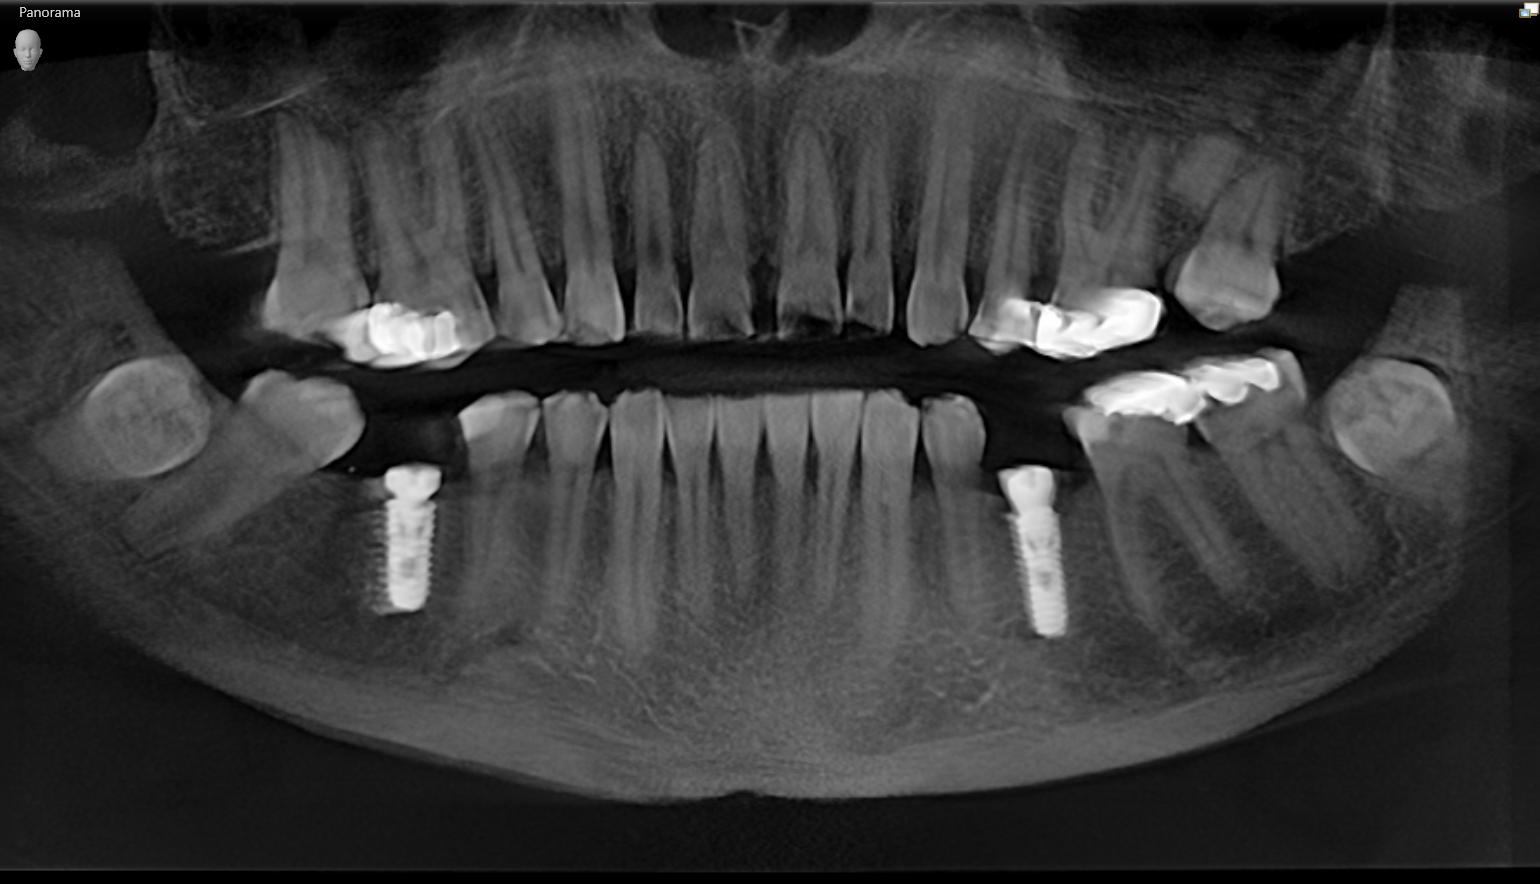

We start with a comprehensive full mouth examination, digital X-rays, a dental 3D(CBCT) scan and Trios5 Scan. The scanned images provide high-resolution images in a three dimensional plane. We use these images and scans for precise treatment planning.

CBCT 3D Scan

Using the 3D images in special planning software, the Dentist maps out the exact position and angle of insertion of each implant. They take care to place implants where they will be stable and in the best position to support the replacement teeth. They will also plan out any bone grafting (if needed) to ensure the implants have strong bone support.

Surgical Guides to Ensure Accuracy of Placement

We manufacture and use a surgical guide to aid in efficient, accurate and minimally invasive implant placement. A surgical guide is a template that fits over the dental arch and marks exactly where and at what angle to place each implant.